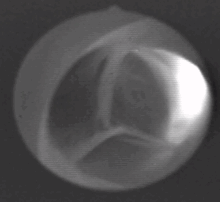

The aortic valve is a valve in the human heart between the left ventricle and the aorta. It is one of the two semilunar valves of the heart, the other being the pulmonary valve. The heart has four valves and the other two are the mitral and the tricuspid valves. The aortic valve normally has three cusps or leaflets, although in 1–2% of the population it is found to congenitally have two leaflets.[1]

The aortic valve normally has three cusps – a left, right and posterior cusp.[2]